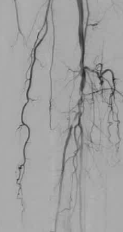

* 需要预防性抗生素 在介入放射学(IR)中,预防性使用抗生素的做法十分普遍;然而,这种做法是基于外科文献中的数据。尽管已发布的指南有助于确定接受经皮操作的患者是否需要预防性使用抗生素,但当地的实际操作模式往往决定了何时使用此类药物。Khurana 2022 介绍了在常见的 IR 操作(即饲食管和导管置入)中围手术期抗生素使用的现状。 清洁 Clean Class I ![]() ![]() ![]() ![]() 污染切口 contaminated Dirty ![]() ![]() 1. 预防(无菌条件)>> 预防性治疗(抗生素)>> 治疗(抗生素、引流……) 2. 预防性使用抗生素的时机影响重大:术前应用可使总体感染率降低约一半,与术后 30 分钟给药相比;术前 30 分钟给药比更早给药感染更少(例外:万古霉素、氟喹诺酮类) 半衰期可能会影响预防用药的持续时间 3. 单次短程预防用药往往与完整的 5 天抗生素疗程效果相当 4. 合理选择抗生素可减少滥用和不良副作用